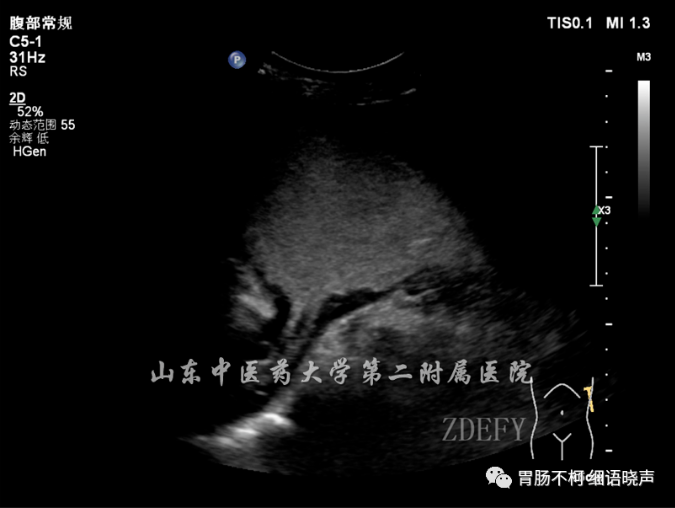

病例二,胃角处胃壁增厚性病变,层次不清晰,回声偏低: